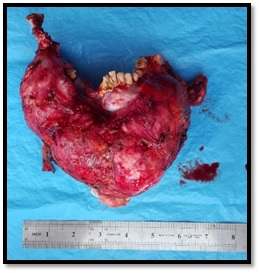

Pathology

On gross examination, the tumor had the shape of the mandible and was convex. On sectioning, the tumor showed a heterogeneous structure with a cystic component containing light-brown transparent fluid. The tumor measured 15×12×10 cm and was sent for histological examination (Figure 6).

Gross specimen. Resected tumor. Figure 6: Gross specimen. Resected tumor.